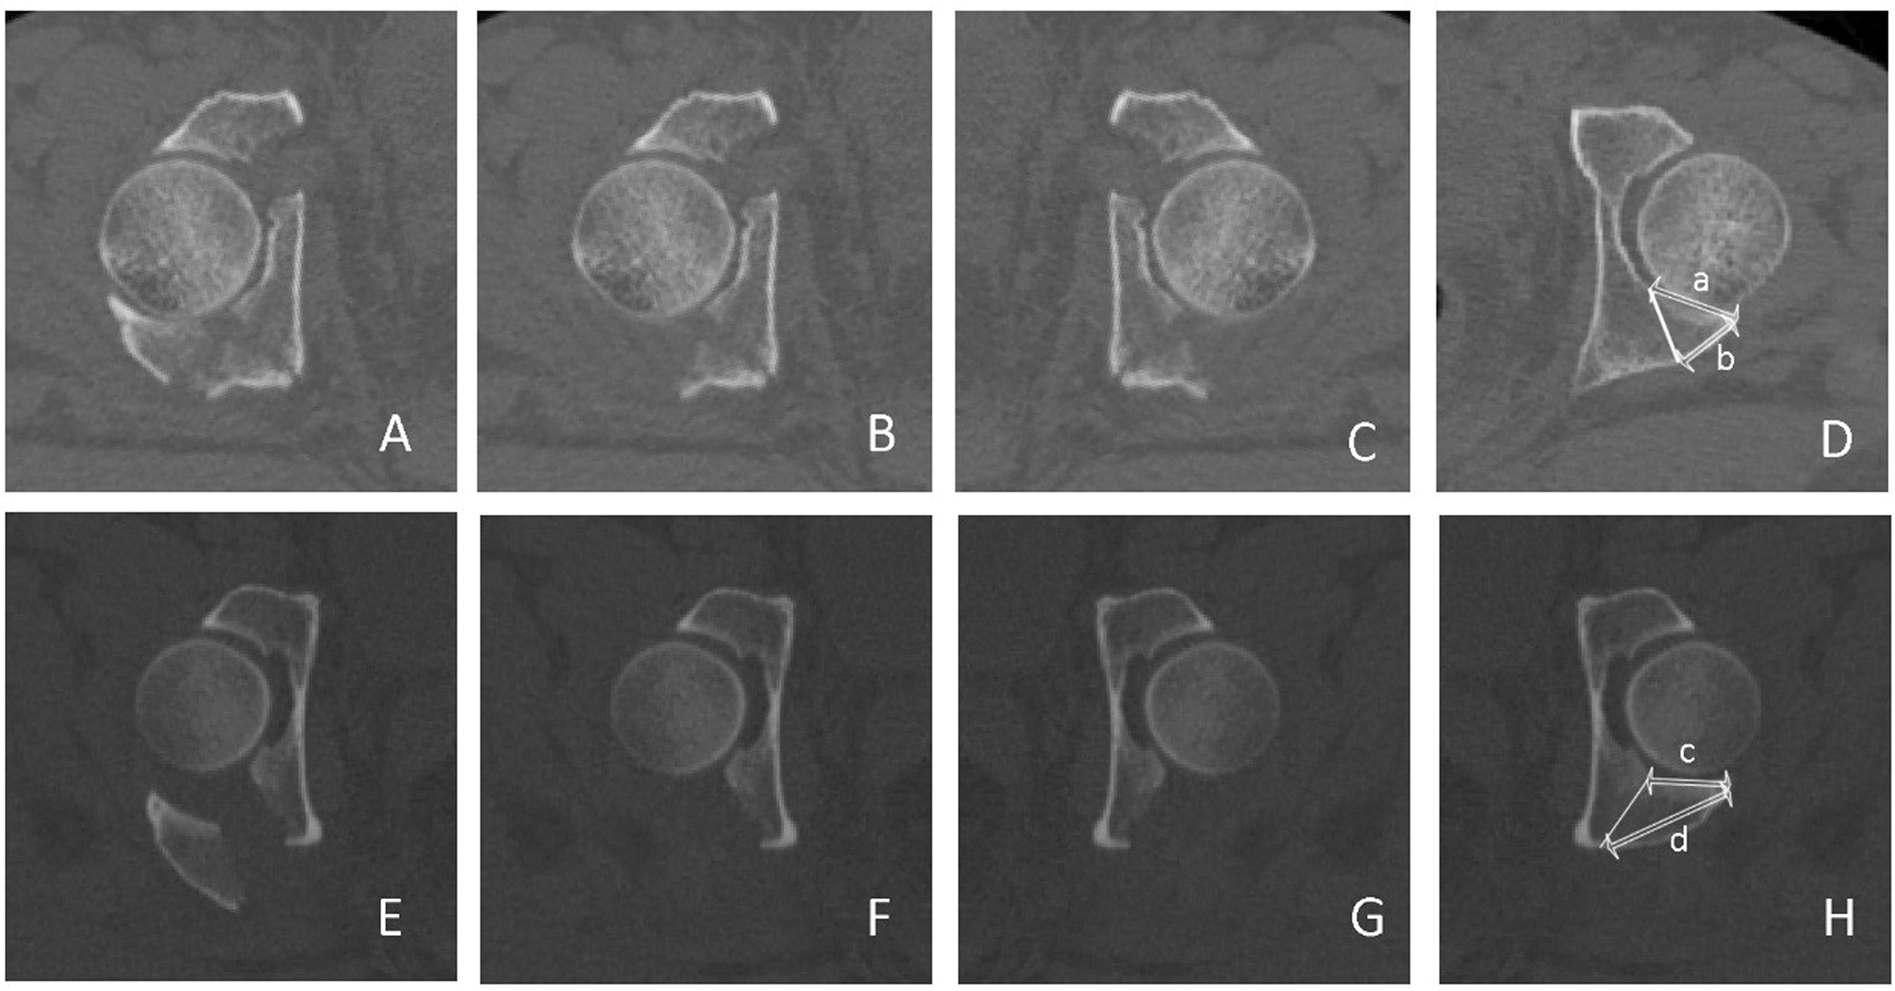

Figure 3

Articular surface-posterior cortex ratios of group (A) (Associated PW) and group (B) (Isolated PW). (A,E) Axial CT sections of the injured acetabulum; (B,F) Injured acetabulum without the fracture fragment of the posterior wall. (C,G) The reversed copies from (B,F), respectively. (D,H) Selected CT sections matching the uninjured acetabulum and simulating a fracture line. The lengths (a–d) were measured between the internal and posterior cortex, respectively.